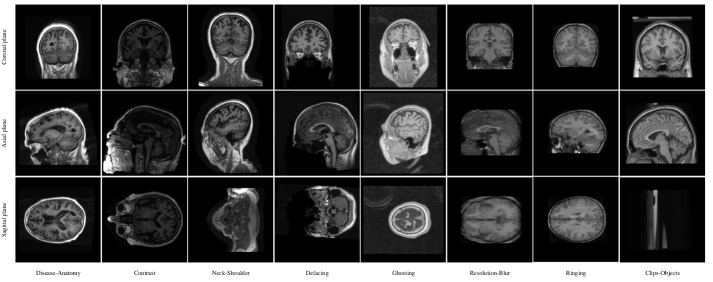

In this section, all the utilized preprocessing and augmentation techniques are described. We have mainly focused on data augmentation and attempted to use very few preprocessing steps to accelerate the training convergence and testing phase and make the models robust to domain shift, which can drop the generalization accuracy due to the differences in the test data (see Figure 3). All of the utilized transforms are 3D and fast and can be applied on the fly during training to the original scans, making the network eligible for online learning. The source codes of the developed tool for generating realistic distortions or deformations on the MRI scans are made publicly available at https://github.com/Mostafa-Ghazi/MRI-Augmentation.